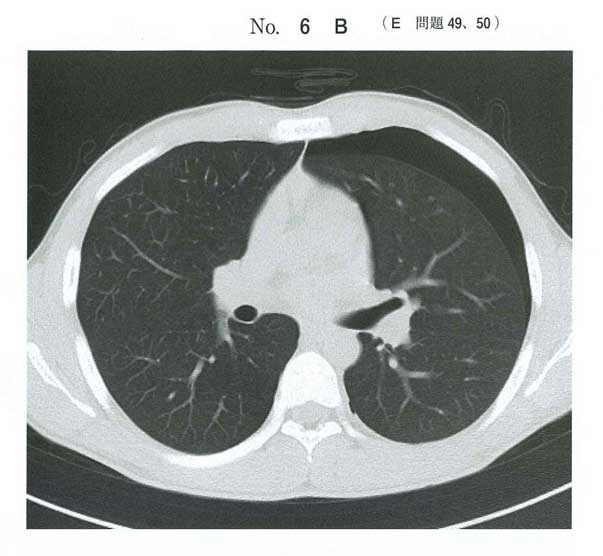

119D60(15問前!)では同じ気胸に対してドレナージを選ばせています。(外傷性であること、SpO2下がってて呼吸おかしくなる可能性高いからだとは思いますが。)

選択肢的にabdは気胸に治療ではない。eはやる可能性はあるにしてもドレナージして効果乏しければ実施。なのでドレナージか経過観察。

今回はそこまでひどい症状じゃないので経過観察かなと思いました。

>大きな変化は認められなかった

ここで大丈夫ですよアピールしていますね

c 外来で経過観察

実臨床では大きな変化がなければ外来で経過観察しています.疼痛あればカロナール等を処方しております.